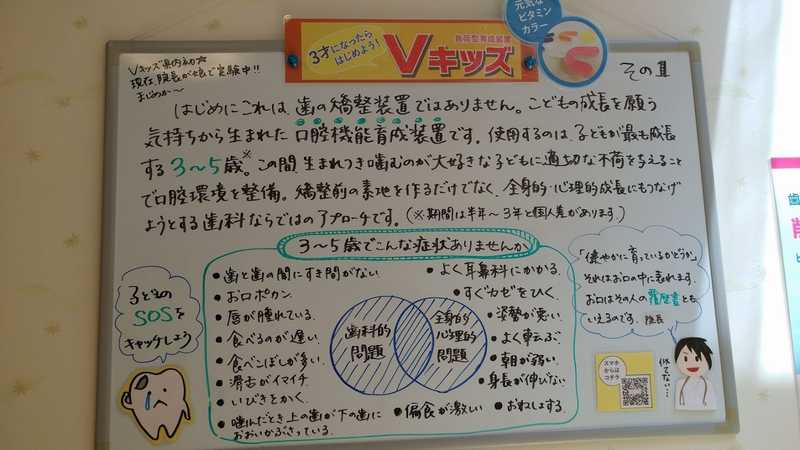

コロナ禍、意外にご質問の多いのがホワイトニングとVキッズです。

ではVキッズはなぜ? 昨今、家族で過ごす時間が増えました。そうすると親としては自然と我が子に目が行きます。そしてなかなか外で遊ばせられない中、心身はちゃんと育っているのか心配になるのではないかと。(実は私がそうでして…)いびきをかいてたり、寝起きが悪かったり、お口ポカンだったり、食べこぼしが多かったり。ちょっとしたことが気になって我が家では、私「あんた、また口あいとるよ。」、子「いいが!!」、こんなトゲトゲしいやり取りが日常化しています。トホホ・・・。みなさんのご家庭はいかがでしょうか…。

「Vキッズの取り組みを掲載しませんか」という依頼を受けたのは去年12月。「えー?!どうするどうする?(驚いてあたふたする)少し考えさせてもらう?っていうか断る理由??…どこにもないな。コロナ禍でヒマだし。」ということで、院長ノリノリで執筆活動開始(笑)。導入のきっかけ~具体症例~考察を赤裸々に綴っています。

スタッフとしても子どもの成長を見ると「未来は明るい」って嬉しくなります。Vキッズをもっと多くの人に知って喜んでもらえたらいいな。

昨年は6月に小児口腔機能育成装置「Vキッズ」、11月にがんリスク検査「サリバチェッカー」を導入しました。患者さんや院長、スタッフ間で日々いろんな話をする中でニーズをくみ取り、それを実践・展開する面白さを感じ毎日充実しています。さあ2020年はどんな変化がうまれるでしょうか、わくわくしています。

これまで水族館みたいなお魚模様の壁だったキッズルーム。プロジェクターを使いたいこともあり少し薄暗い雰囲気でしたが、このたび気分新たにパステルカラーの明るいお部屋に大変身しました。採用したのは当院のロゴにもなっている淡い4色。四角い部屋の壁面ごとに色が違います。そして一番のこだわりポイントは身長計があるところ。「小児口腔機能装置Vキッズ」の治療で子どもたちの身長を測るので取り入れることにしました。

2019.8『Vキッズ導入から1カ月』

大人はいつでも子どものことを考え、幸せを願っているのだな…と最近実感しています。

6月スタートした『Vキッズ』。院内では待合室と診察室、2か所の掲示板で紹介しています。それを見た多くの方が「これは一体何なのか」と質問していかれ、わずか1カ月間で「ぜひ我が子に試したい」と挑戦する方が増えているのです。

これは大人が忙しい中でも日々子どもを見つめ、我が子にとっていい情報はないか、常にアンテナを張っている証だと思います。正直、こんな田舎の診療所に最先端の医療があるとは誰も思っていないことでしょう。常に探し求めていないと素通りしてしまうはずです。しかも決して安くはない買い物です。にも関わらず即決される方がほとんどです。

そもそも院長が最初に装置を作ったのが娘さんにでした。我が子のために一生懸命です。そんな姿勢に人は共感されるのでしょう。子どもの幸せを思う気持ちはみな同じなのですね。